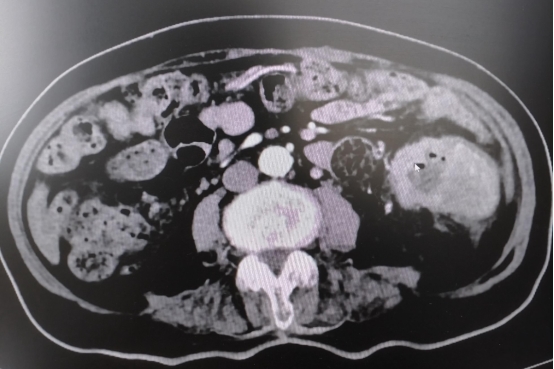

80岁的老奶奶在一年前就出现了排便异常、贫血,但因年龄较大,且伴有糖尿病、冠心病等基础疾病,忽视了这些征兆,也一直未进行肠镜检查。直到近期,奶奶症状突然加剧,已经出现严重的头晕、气喘,经检查发现重度贫血,输血后,我院肠镜检查确诊其为降结肠肿瘤,且肿瘤已导致肠道不通畅,CT进一步显示肿瘤已出现肝转移。

专家们全面分析后认为:大肠肿瘤不解决,患者将无法正常排便、进食,持续出血会加重贫血和营养不良;一旦出现肠道完全梗阻或肿瘤穿孔,治疗效果更差。与患者家属充分沟通后,团队决定先行手术切除肿瘤,解除出血及梗阻问题,待老人身体状况改善后,再针对肝转移病灶进行后续治疗。